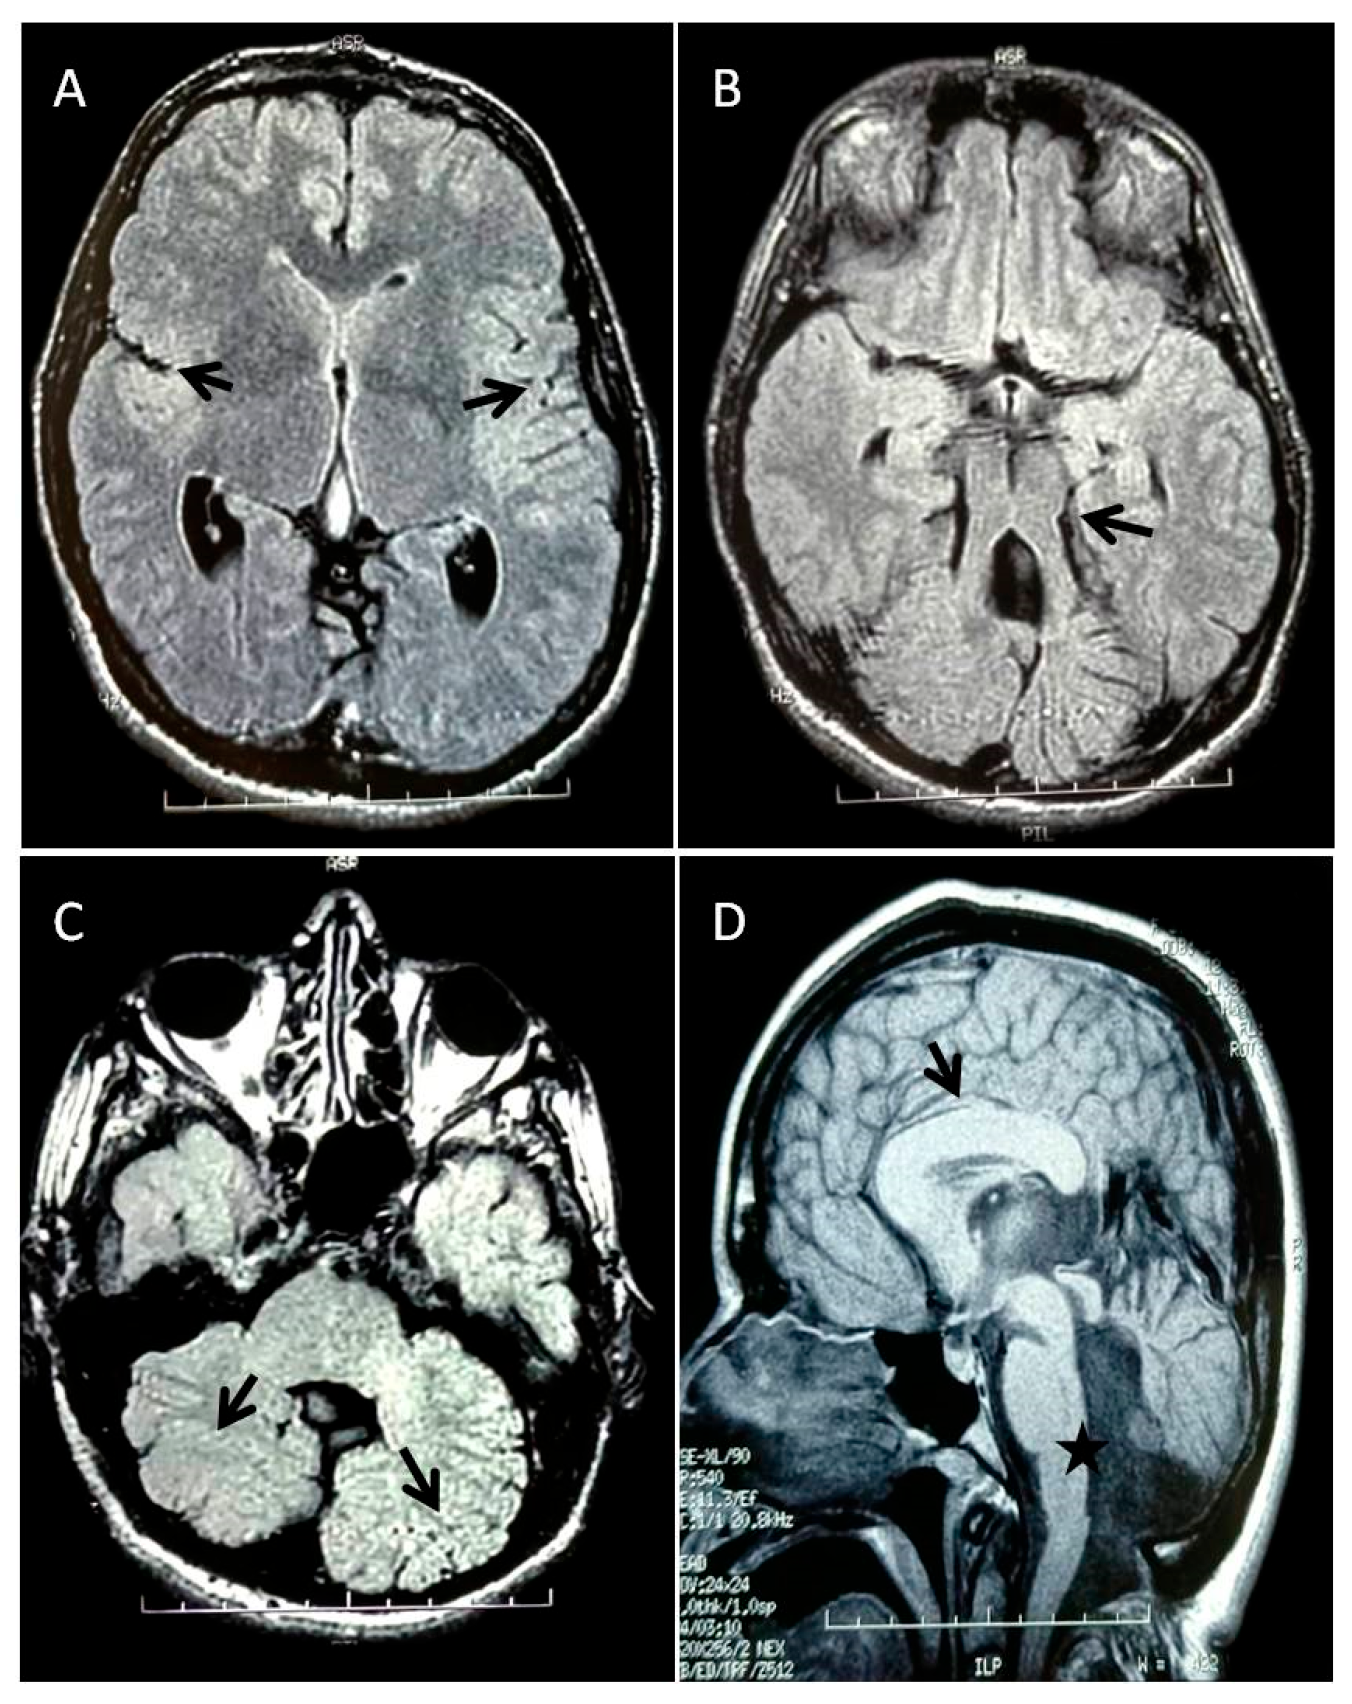

3.1. Patient’s Clinical History